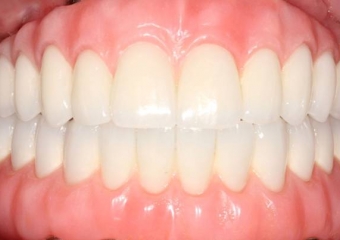

Próteses fixas em porcelana sobre implantes - Clínica Cliniface

Próteses fixas em porcelana sobre implantes

Sorriso final do caso terminado em Dezembro de 2011 - Clínica Cliniface

Sorriso final do caso terminado em Dezembro de 2011